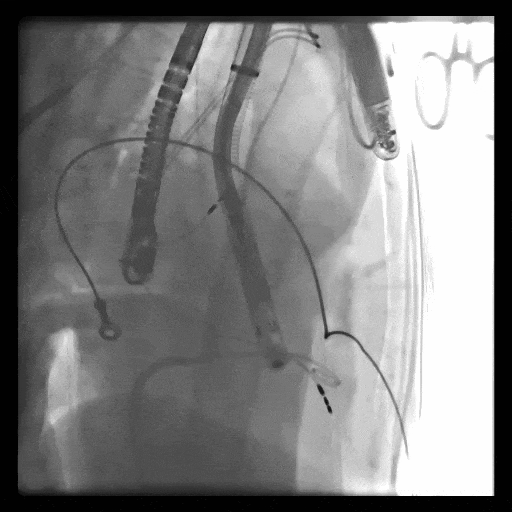

術(shù)中DSA顯示起搏器導線的干擾,右心室造影確定瓣環(huán)位置,操作空間小